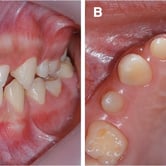

Desgaste dental (Abfracción)

La abfracción es la pérdida de esmalte dental en la región cervical del diente, generalmente causada por fuerzas oclusales excesivas.

Los pacientes pueden notar hendiduras o surcos en la base de los dientes. Esta condición puede causar sensibilidad y aumentar el riesgo de caries.

El tratamiento incluye ajustes oclusales y restauraciones dentales.